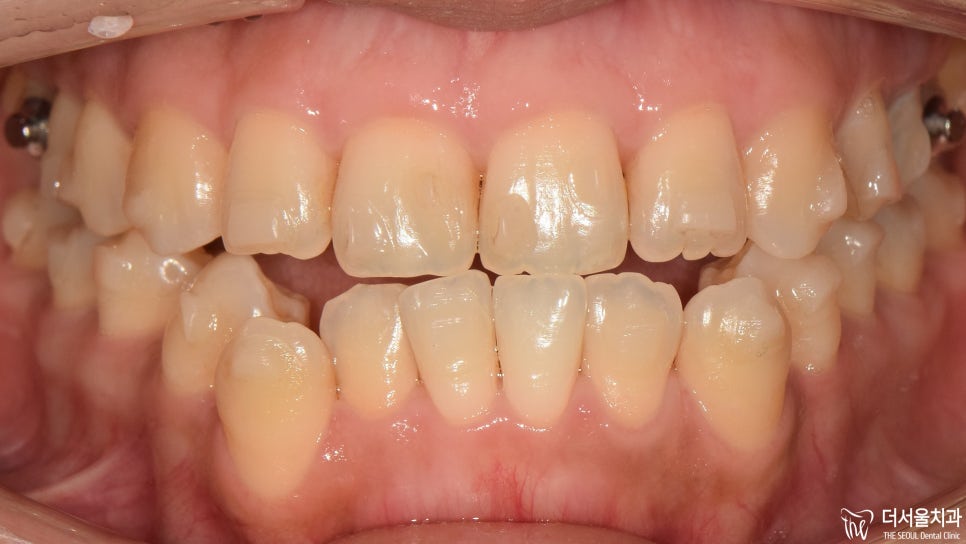

『과연 결과는 어떻게 나왔을까?』

제작된 인비절라인 과 어태치먼트의 도움을 받아

원하는 곳으로 신속하게

움직일 수 있도록 유도했습니다.

자 기나긴 교정 기간이 끝나고

드디어 마무리를 하는 날이 찾아왔습니다.

전과는 달리 제위치를 찾아간 치아들이 눈에 띕니다.

골격은 아직 Class 3급이라

완벽한 어금니 교합은 어려웠는데요.

이제는 입을 다물 때 힘을 주지 않아도

자연스럽게 다물어지기에

환자께서도 만족해하셨죠ㅎㅎ

주걱턱 때문에 스트레스를 많이 받으셨던 분인데요.